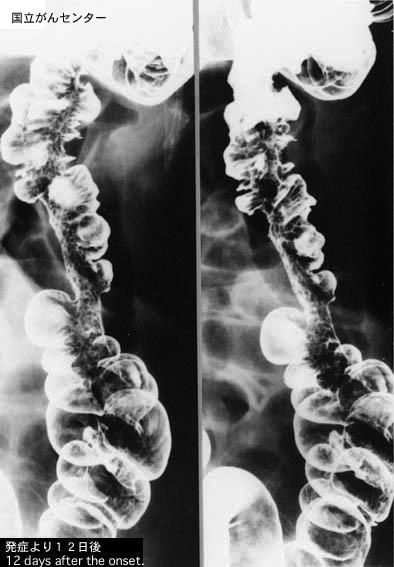

외국에서 진행대장암으로 진단된 허혈성 대장염

염증성 및 궤양성질환/허혈성 장염(혈전증 포함)

대장/하행

X-P

40이상